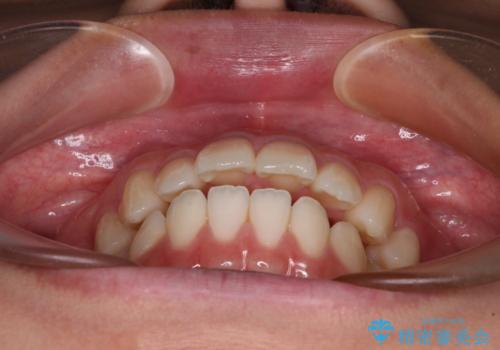

- 口元の突出感と上下前歯のズレを気にして来院された患者様です。

舌の突出癖により上下の前歯は非接触となっている状態でした。

舌のトレーニングを行わないと上下前歯の接触達成は困難であるため、トレーニングをしっかりと行っていただきながら、治療を進めて行くこととしました。

突出感改善のため、上下左右の第一小臼歯4本を抜歯し、ワイヤー装置にて矯正治療を行うこととしました。